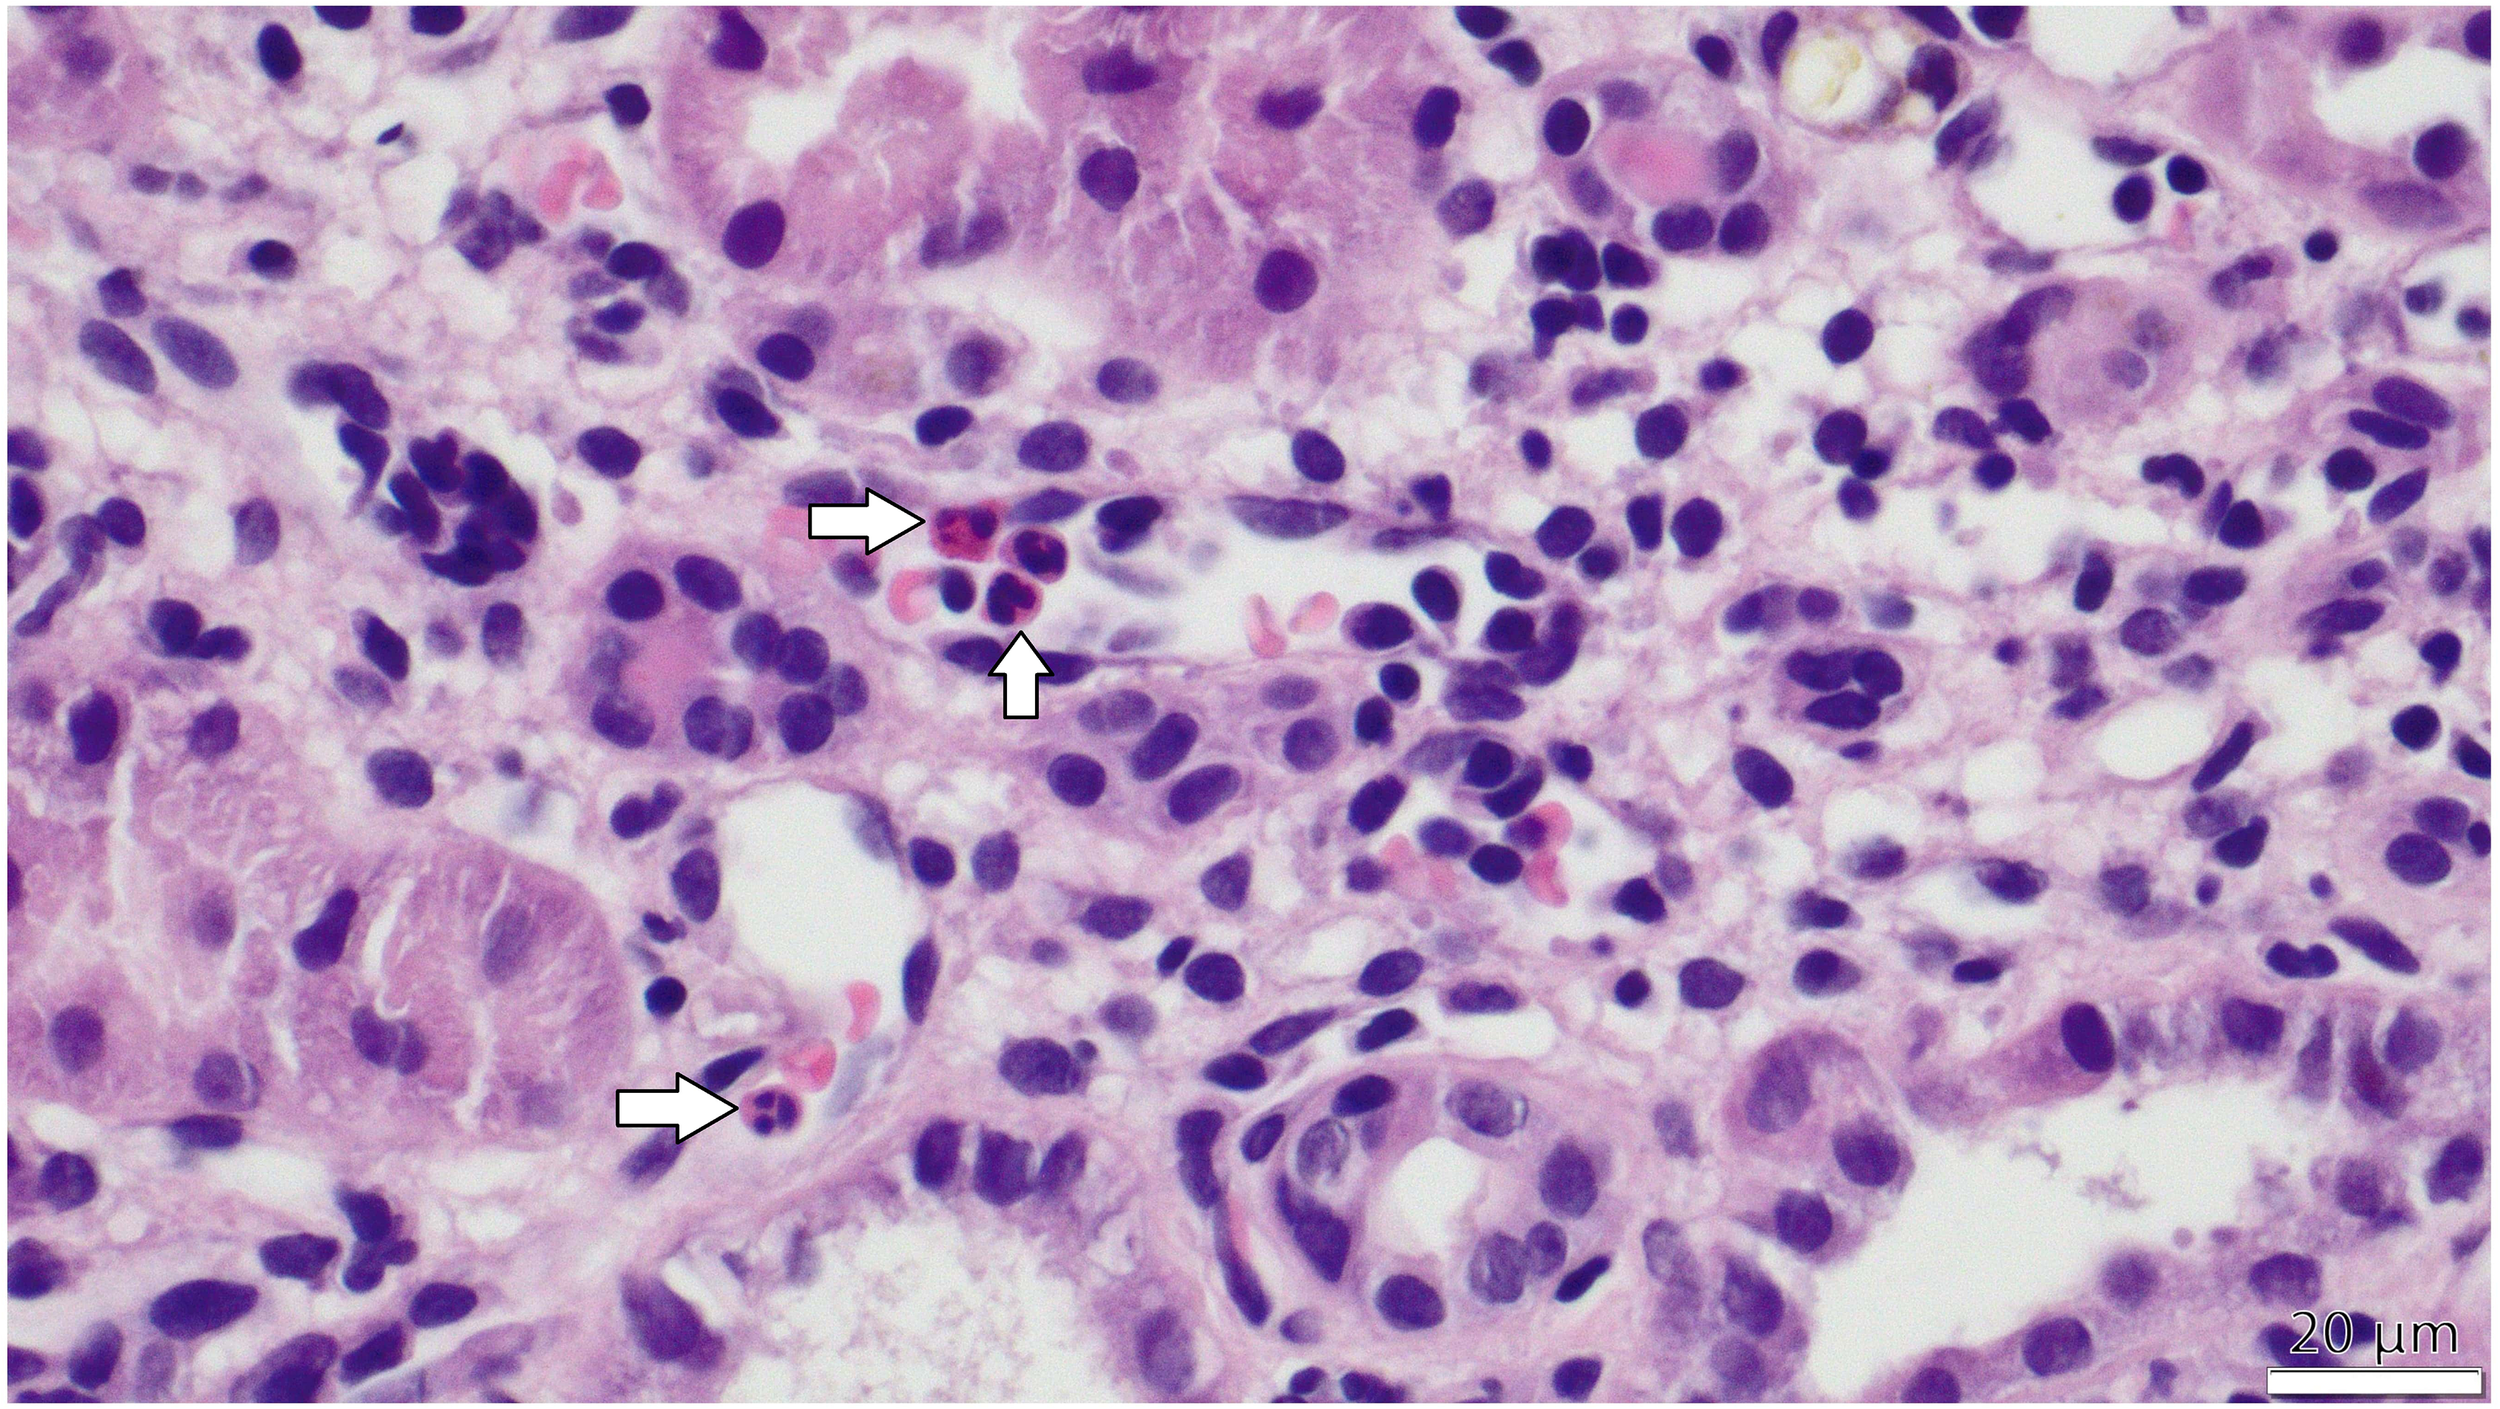

Figure 2

PTC-itis (microvascular inflammation) -The image taken via light microscope demonstrates a section of the renal cortex from a transplanted kidney, stained with hematoxylin and eosin (H&E). Multiple peritubular capillaries are visible adjacent to renal tubules, showing prominent infiltration of inflammatory cells, primarily mononuclear leukocytes and scattered neutrophils, identifiable by their dark purple-stained nuclei within the capillary lumens. White arrows in the figure indicate the inflammatory cells within capillary lumens.